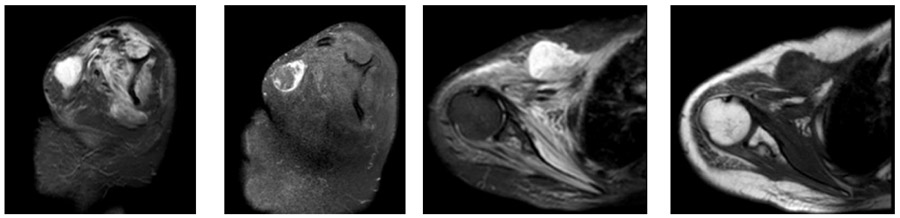

Ameliyat Öncesi: MR’da omuz ön kısımda yerleşmiş düzensiz sınırlı heterojen kitle görülmekte